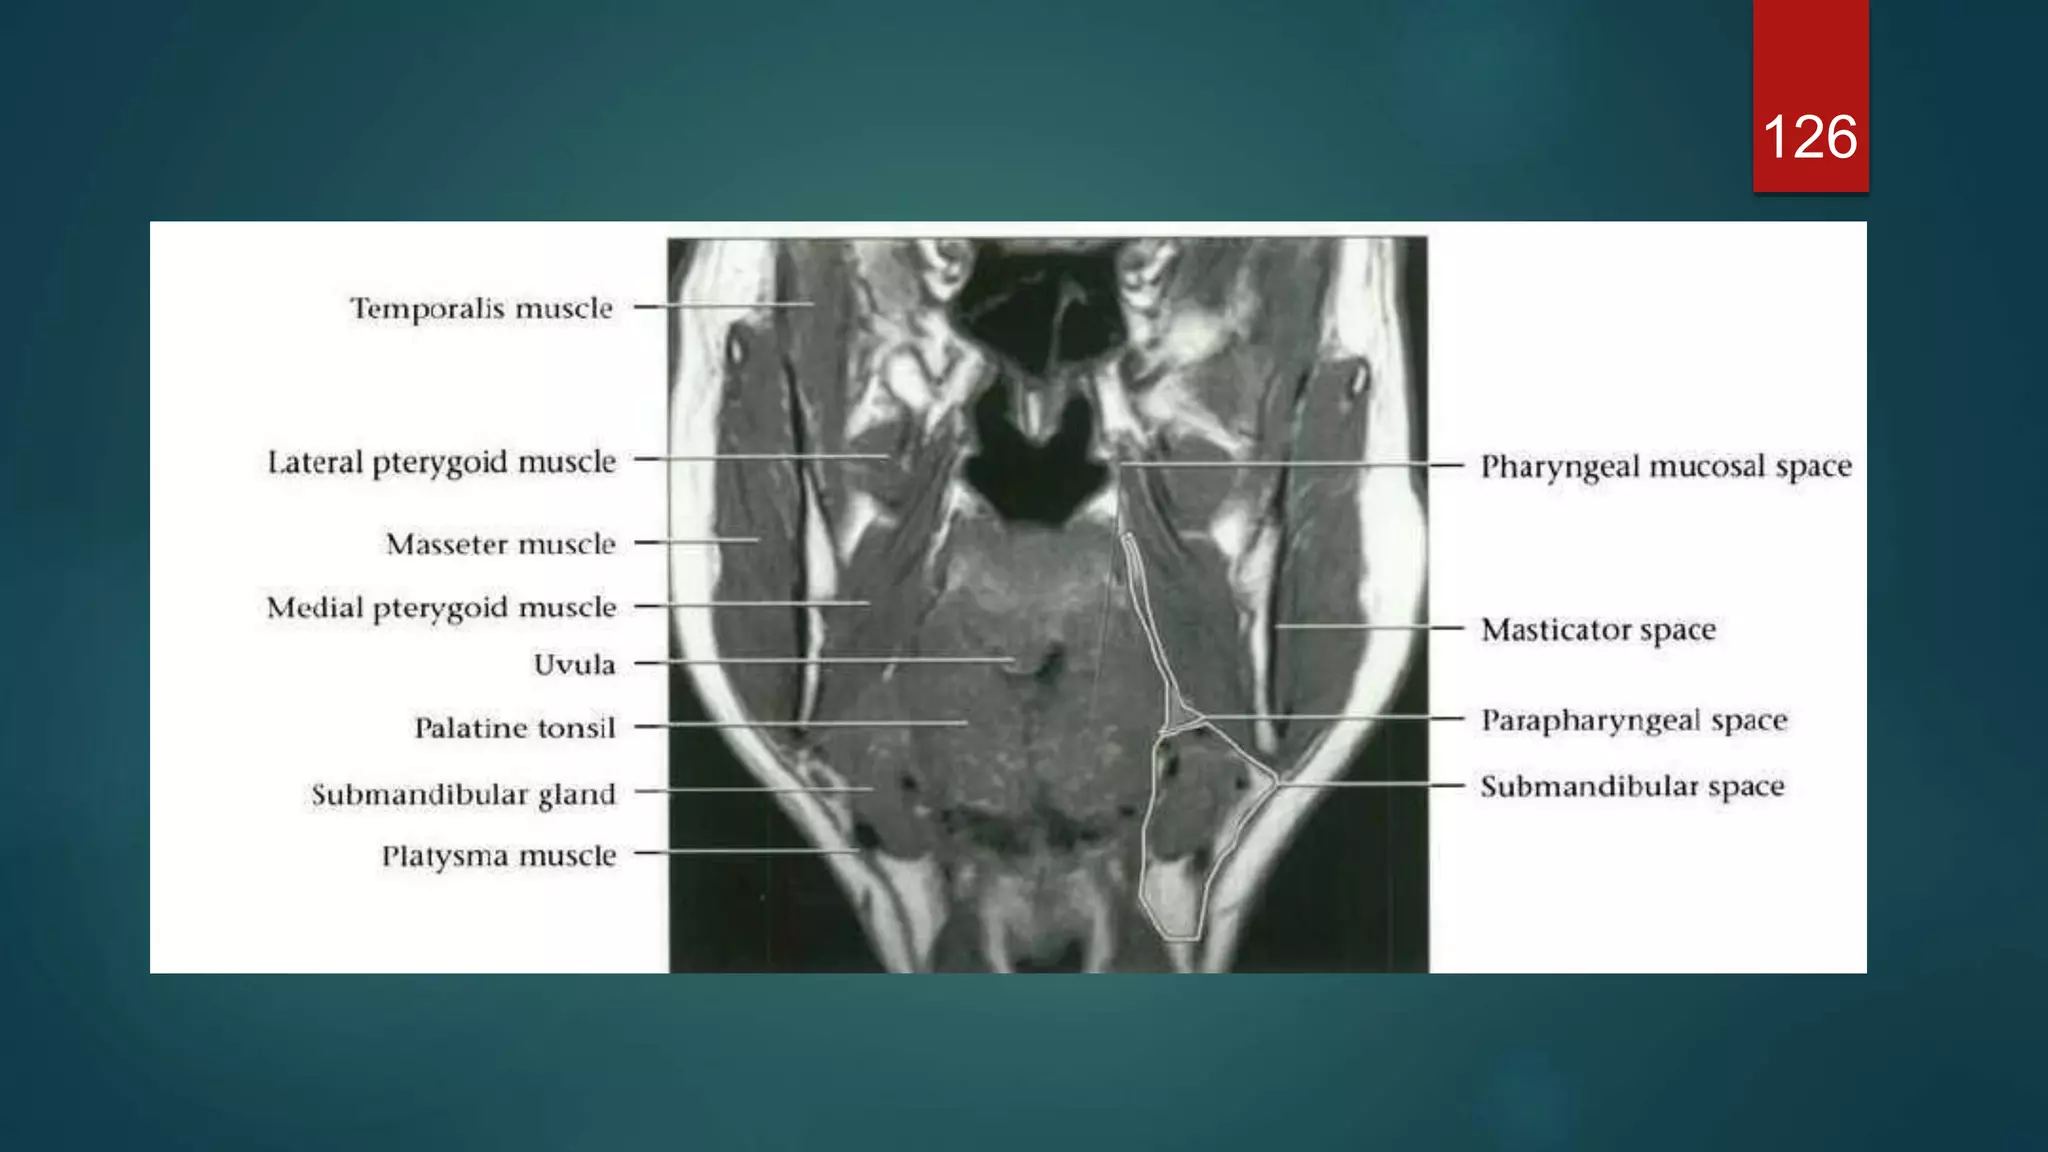

MASTICATOR SPACE

 The masticator space are paired suprahyoid cervical spaces on each

side of the face. Each space is enveloped by the superficial (investing)

layer of the deep cervical fascia.

 The superficial layer of deep cervical fascia splits into two at the lower

border of the mandible, the inner layer running deep to the medial

pterygoid muscle and attaches to the skull base medial to foramen ovale

and the outer layer covering masseter and temporalis muscles and

attaches to the parietal cavarium superiorly.

 Extends from skull base to the inferior edge of the mandible.

 Contents

• muscles of mastication

• ramus and body of mandible

• inferior alveolar nerve

• inferior alveolar vein and artery

• mandibular division of the trigeminal nerve (V3): enters the

masticator space via the foramen ovale

 Boundaries and relations

• anteriorly: buccal space

• posterolaterally: parotid space

• medially: parapharyngeal space

SUBMANDIBULAR SPACE

 Extend : Mylohoid superiorly & hyoid

bone inferiorly.

 Communicates freely with sublingual

space.

 Contents : superficial portions of the

Submandibular gland, submental and

submandibular LNs, facial artery and

vein, fat and ant belly of digastric.

PHARYNGEAL MUCOSAL SPACE

 The pharyngeal mucosal space is the most internal compartment (closest

to the airway) of the seven deep compartments of the head and neck,

delineated by the middle (pretracheal) layer of deep cervical fascia . It

extends from the base of the skull to the cricoid cartilage.

PARAPHARYNGEAL SPACE

 The parapharyngeal space is shaped like

a pyramid, inverted with its base at the

skull base, with its apex inferiorly

pointing to the greater cornu of the hyoid

bone.